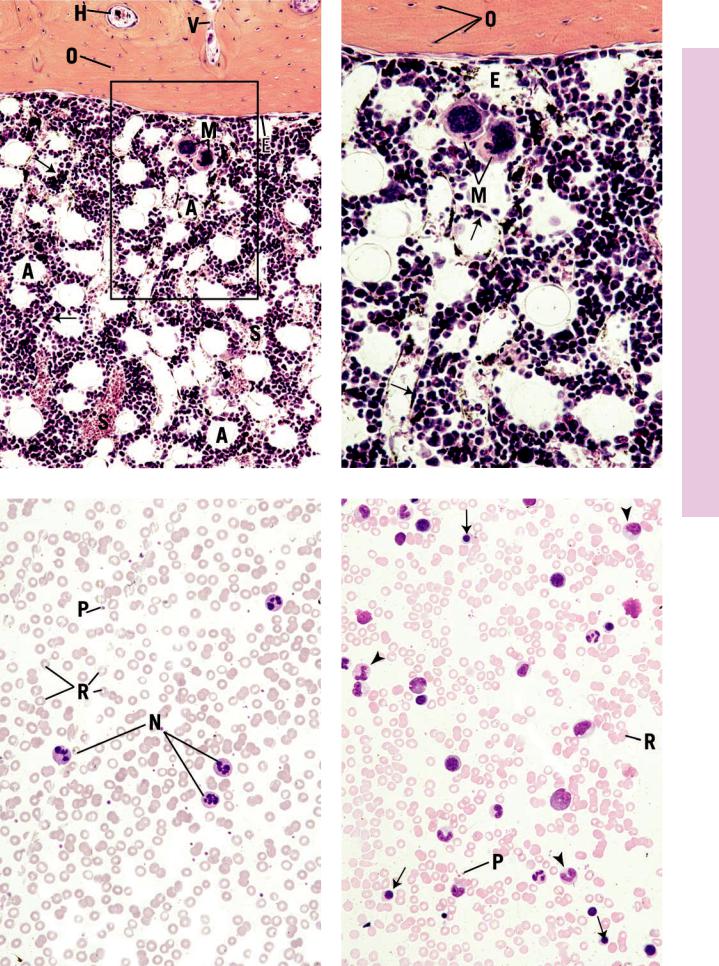

Erythropoiesis • 5-5 PLATE

FIGURE 1. Human marrow smear. ×1,325.

Proerythroblast.

FIGURE 2. Human marrow smear. ×1,325.

Basophilic erythroblast.

FIGURE 3. Human marrow smear. ×1,325.

Polychromatophilic erythroblast.

FIGURE 4. Human marrow smear. ×1,325.

Orthochromatophilic erythroblast.

FIGURE 5. Human marrow smear. Methylene blue stain. ×1,325.

Reticulocyte.

FIGURE 6. Human marrow smear. ×1,325.

Erythrocyte.

1.15 cm = 7.5 µm